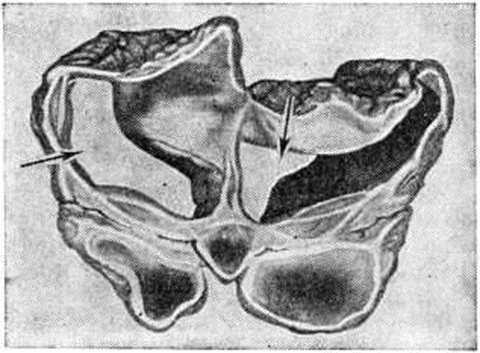

ГидроцефалияГидроцефалия (hydrocephalus; греческий hydor вода + kephale голова; синонимы водянка головного мозга) — состояние, характеризующееся избыточным накоплением цереброспинальной жидкости в желудочках мозга и подоболочечных пространствах. Гидроцефалия является следствием различных заболеваний или травм головного мозга и его оболочек. КлассификацияНаибольшее распространение в СССР получила классификация, предложенная А. А. Арендтом в 1948 год. В ней Гидроцефалия рассматривается в зависимости от времени возникновения, течения, этиологического факторов, локализации и характера нарушения функции ликворного аппарата. По времени возникновения различают врождённую и приобретённую Гидроцефалия, по течению — острую и хроническую. По локализации выделяют наружную и внутреннюю Гидроцефалия При наружной Гидроцефалия имеется избыточное скопление цереброспинальной жидкости преимущественно в субарахноидальных пространствах, при внутренней — в желудочках головного мозга. Нередко наблюдается комбинация внутренней и наружной Гидроцефалия — так называемый общая Гидроцефалия По характеру нарушения функции ликворного аппарата принято различать открытую (сообщающуюся) и закрытую (окклюзионную) Гидроцефалия Открытую Гидроцефалия в свою очередь подразделяют на гиперсекреторную, при которой секреция цереброспинальной жидкости значительно повышена, и арезорбтивную, характеризующуюся нарушением её всасывания. При окклюзионной Гидроцефалия имеется нарушение на различных уровнях оттока цереброспинальной жидкости из желудочков в субарахноидальные пространства в результате спаечного процесса, кист, опухолей и так далее. Встречаются смешанные формы Гидроцефалия, когда окклюзия ликворных путей сочетается с нарушением резорбции или секреции цереброспинальной жидкости. Этиология и патогенезРазличные поражения головного мозга и его оболочек могут привести к Гидроцефалия Чаще всего она наблюдается после инфекционных заболеваний (гнойный эпидемический цереброспинальный менингит, вторичные менингиты и менингоэнцефалиты) и черепно-мозговых травм. Кроме того, Гидроцефалия может возникнуть при затруднении оттока крови из полости черепа (патология венозной системы, тромбоз синусов, сдавление рубцами и спайками отводящих вен), при опухолях, а также при гипертензии, заболеваниях почек и паразитарных поражениях головного мозга. Иногда Гидроцефалия возникает в результате аномалии развития головного и спинного мозга (недоразвитие мозга, мозговые и спинномозговые грыжи и так далее). Вышеперечисленные причины могут привести к нарушению секреции, всасывания или циркуляции цереброспинальной жидкости с последующим развитием Гидроцефалия Патологическая анатомияМорфологически изменения в мозге и оболочках при Гидроцефалия зависят как от основного заболевания, приведшего к Гидроцефалия, так и от длительности повышенного внутричерепного давления. Как правило, наблюдается расширение полостей желудочков, особенно боковых, за счёт увеличения в них количества цереброспинальной жидкости (рисунок 1). Боковые желудочки расширены симметрично как при открытой, так и закрытой Гидроцефалия с окклюзией межжелудочковых отверстий водопровода мозга и апертур IV желудочка (рисунок 2—4). |

Асимметричное расширение желудочков чаще всего наблюдается при закупорке одного межжелудочкового отверстия или на стороне травмы. Прогрессирующее увеличение желудочков приводит к атрофии мозговой ткани, уплощению извилин и сглаживанию борозд мозга. Рано поражаются пирамидные пути. Изменению подвергается прежде всего белое вещество, мозолистое тело и свод. Изменение серого вещества наблюдается при Гидроцефалия в результате травмы и в тяжёлых случаях Гидроцефалия. При врождённой Гидроцефалия может нарушаться строение коры. Атрофия нервной ткани при Гидроцефалия, по мнению У. Пенфилда и Элвиджа (A. Elwidge, 1932), Б. Н. Клосовского (1949), В. П. Пурина (1968), происходит в результате сдавления капилляров мозга вследствие внутричерепной гипертензии. Выраженная астроцитарная реакция в белом веществе при Гидроцефалия является плохим прогностическим признаком. Кроме изменений со стороны ткани мозга, при Гидроцефалия отмечают выраженные изменения и со стороны сосудистых сплетений, эпендимы желудочков и его оболочек. Наблюдается атрофия сосудистых сплетений с фиброзным перерождением их соединительнотканной основы и гибелью эпителия. При Гидроцефалия после инфекционных заболеваний выявляют признаки гранулематозного эпендиматита (смотри Хориоэпендиматит). Мозговые оболочки резко утолщены, мутны, отёчны. Отмечают их фиброз, сращение главным образом в области базальных цистерн основания мозга, большого затылочного отверстия и апертур IV желудочка. В оболочках выявляют воспалительные инфильтраты. При травматической Гидроцефалия в мозге находят следы бывших кровоизлияний, рубцы в местах некрозов мозговой ткани, спайки в области путей оттока цереброспинальной жидкости и так далее. В сосудах головного мозга при Гидроцефалия обнаруживают признаки артериосклероза с гиалинозом сосудов.

Рисунок 2. | ||